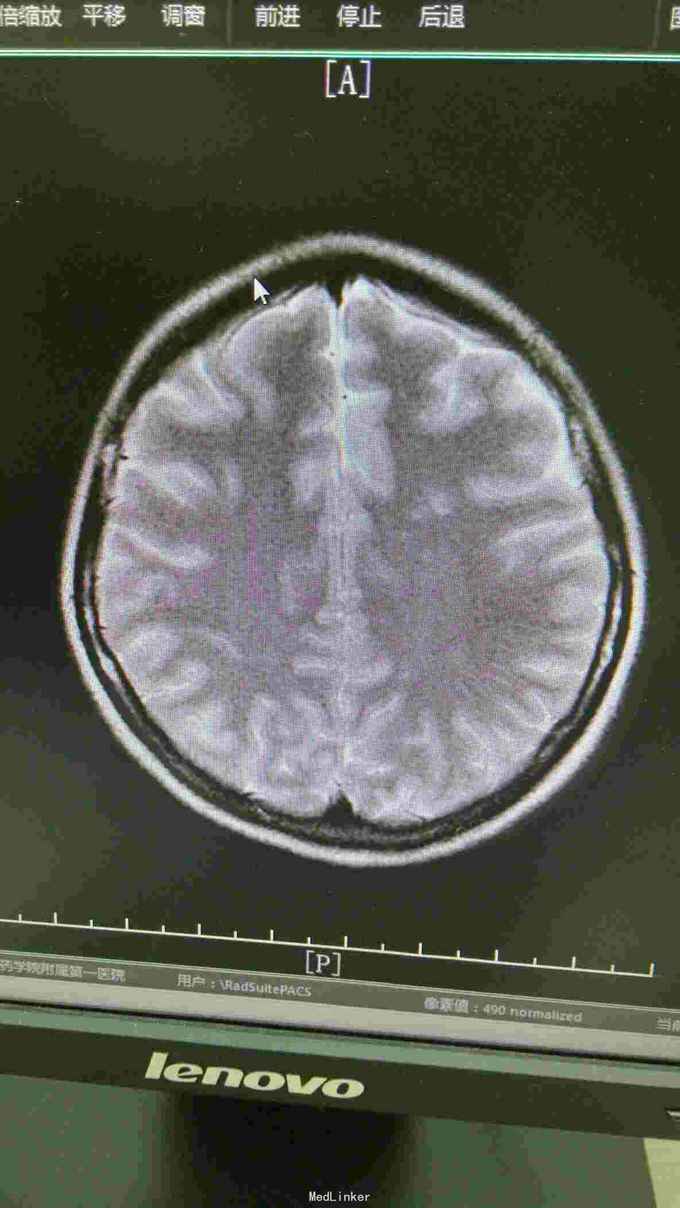

查体:T37.0℃,P110次/分,R26次/分,BP96/68mmHg。发育正常,营养一般,神志清楚,对答切题,轮椅送入院,查体合作。全身皮肤粘膜无黄染、皮疹,出血点及淤斑,未见Janeway结节,未见Osler结节及甲床下出血,无发绀,未见杵状指、趾,周围血管征阴性。浅表淋巴结未及肿大。巩膜无黄染,结膜无出血。口腔黏膜光滑,咽不红,扁桃体部大,颈静脉无明显搏动,未见怒张,气管居中,胸背部听诊双下肺闻及细小湿啰音。心前区无隆起或抬举性搏动,心尖搏动以左侧第六肋间锁骨中线外1.5cm处明显,未扪及震颤,心界向两侧稍扩大,心率110次/分,律齐,心音有力,P2稍亢进,无固定分裂,心尖区闻及3-4/6级收缩期吹风样杂音,向心底部传导,未闻及舒张期杂音,未闻及心包摩擦音。腹平软,无压痛及反跳痛,肝脾肋下未及,肠鸣音正常。脊柱、四肢关节无异常,活动好,双下肢无浮肿。 2015年10月30日汕头市中心医院心彩超:二尖瓣及瓣下腱索及左室心内膜多发赘生物形成,二尖瓣前瓣穿孔,重度二尖瓣关闭不全,左心系统扩大,心肌舒张功能下降,收缩功能正常,感染性细菌性心内膜炎,微量心包积液。 2015-11-1血常规:中性粒细胞比例 0.949,血红蛋白浓度 117.000(g/L),中性粒细胞计数 18.360(10E9/L),白细胞计数 19.350(10E9/L),血小板计数 343.000(10E9/L),红细胞计数 4.350(10E12/L)。 B超:双侧颈动脉血流通畅,双侧椎动脉未见狭窄。双侧甲状腺不大、未见占位,血供尚丰富。双侧颈部淋巴结声像,双侧乳腺未见明显占位,超声BI-RADS分类1类,双侧腋窝淋巴结声像。双肾未见结石与积水,双肾动脉主干血流连续,膀胱未见明显结石,双侧肾上腺区未见明显占位。肝脾胰不大,未见占位,胆囊未见明显结石,子宫及双侧附件区未见明显占位,宫后积液(少量)。 胸部CT:1、两下肺叶后基底段局部节段性肺炎。右肺中叶少许纤维化病灶。2、双侧胸腔少量积液。 胸片:考虑双肺炎症。 心电图:心率84次/分,窦性心律,肢体导联低电压,前间壁R波上升不良。 心彩超:1、考虑感染性心内膜炎:二尖瓣赘生物形成,伴中重度二尖瓣反流。中度三尖瓣反流。3、左房内径增大,肺动脉增宽。 头颅MR:左侧额叶、左侧放射冠侧脑室前角旁脑白质异常信号,考虑感染性病变及缺血灶可能性大。 2015-11-2查血常规:中性粒细胞比例 0.840,血红蛋白浓度 103.000(g/L),中性粒细胞计数 14.730(10E9/L),白细胞计数 17.540(10E9/L),红细胞计数 3.890(10E12/L),血小板计数 353.000(10E9/L)。 10月31日左上肢、右上肢、下肢血培养均提示:草绿色链球菌,对万古霉素敏感。 2015-11-6肾功能:肌酐 130.000(umol/L),尿素氮 5.250(mmol/L),二氧化碳结合力 30.500(mmol/L),电解质:钠 138.000(mmol/L),氯 96.000(mmol/L),钾 3.500(mmol/L),钙 2.310(mmol/L),肝功能:白、球蛋白比例 1.300,未结合胆红素 10.500(umol/L),总胆红素 17.900(umol/L),丙氨酸氨基转移酶 31.000(U/L),总蛋白 75.000(g/L),球蛋白 32.000(g/L),白蛋白 43.000(g/L),结合胆红素 7.400(umol/L),门冬氨酸氨基转移酶 31.000(U/L),脑钠肽:191.400(pg/ml)。 24小时心电图:窦性心律,房性早搏,部分成对,短阵房速,多源室早,部分成对,部分呈三联律,短阵室速。

关于感染性心内膜炎此前我发布过一个病例,但不同的病例有不同的特点和经验教训。上次的病例病变范围大,累及多瓣膜,治疗的难度在手术关,因手术过程复杂、手术时间长、对患者全身打击影响大,但上一个病例术前感染控制良好,在全身情况明显好转的情况下手术。此次发布的这个病例赘生物累及的瓣膜无上例多,但本例患者术前感染无法控制,反复高热、寒战,且赘生物大且形态呈“甩鞭样”,随时可能脱落栓塞周围脏器,另头颅MR报告左侧额叶、左侧放射冠侧脑室前角旁脑白质异常信号,考虑已有部分小栓子脱落栓塞脑血管形成小的感染性病变及缺血灶可能性大。因此综合考虑上述因素决定无法等患者全身状态好转在所谓的“理想状态”下手术,必须冒风险尽快行手术治疗,否则患者全身情况会进一步恶化并且可能发生脑栓塞,因此失去手术时机并可能导致死亡。术中需仔细清除干净感染的赘生物,术后积极强心、利尿、支持治疗并且敏感抗生素治疗4周。该病例术后出现反复双侧胸腔积液及心包积液,上一个病例也曾出现胸腔积液,考虑与患者术前全身状况不佳、心功能差及感染性心内膜炎所致的全身败血症及感染微栓有关。